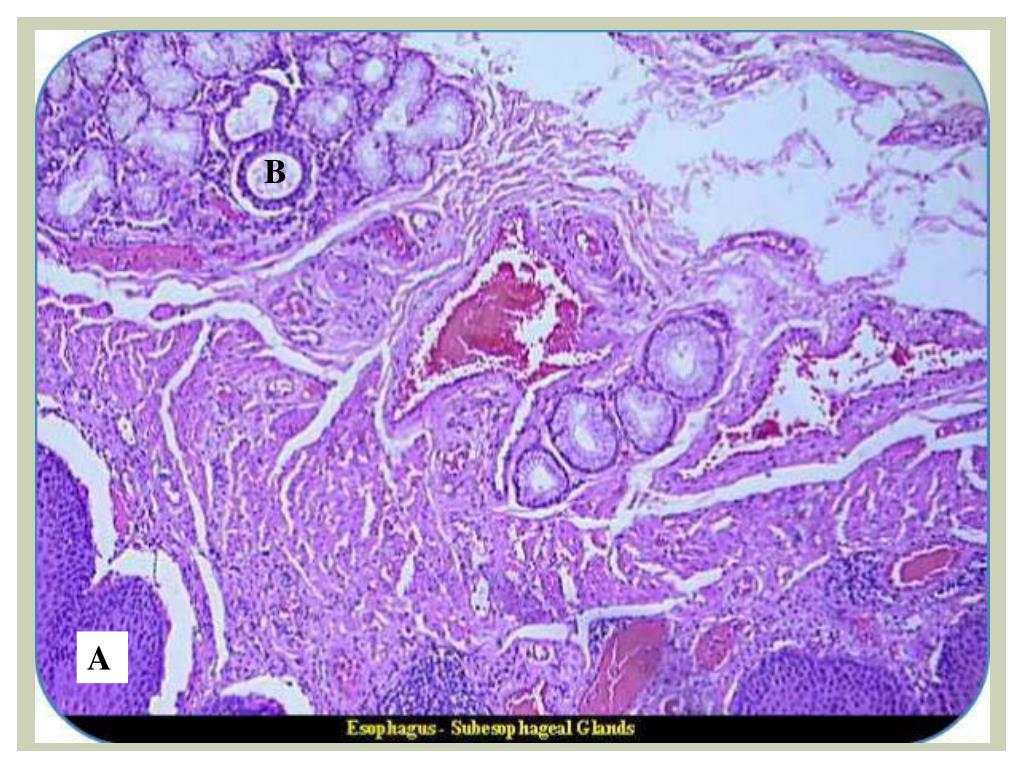

2. Esophagus Stratified squamous epithelium • Submucosa • The muscularisexterna • Esophageal glands.

3. A B C D E

4. B A